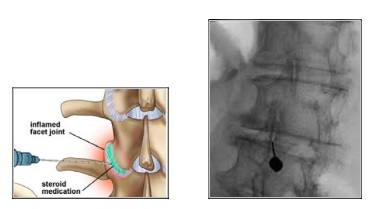

Τι είναι η ενδροαρθρική έγχυση στις αρθρώσεις–Facet της σπονδυλικής στήλης

Πρόκειται για απευθείας έγχυση στεροειδούς στην κάψα που περιβάλλει την άρθρωση. Διενεργείται κάτω από ακτινοσκοπικό έλεγχο στην αυχενική, θωρακική ή οσφυϊκή μοίρα της σπονδυλικής στήλης. Ανακουφίζει από τον πόνο μέσα σε μερικές μέρες και βελτιώνει την κίνηση.

Διενεργείται με τον ασθενή μπρούμητα, υπό τοπική αναισθησία και ως διαδικασία διαρκεί 10-20 λεπτά.

Μια βελόνα εισάγεται απευθείας στο κατώτερο τμήμα της άρθρωσης, όπου χορηγείται το φαρμακευτικό διάλυμα. Η παρέμβαση δεν χρειάζεται νοσηλεία και ο ασθενής μπορεί να επιστρέψει στην καθημερινότητά του την επόμενη μέρα.